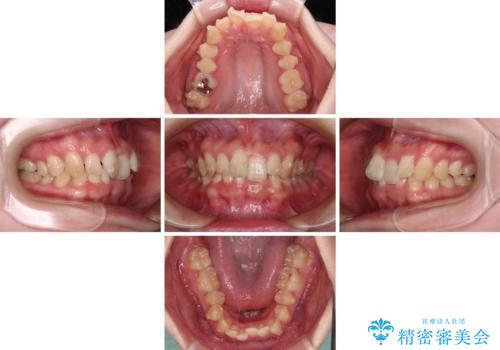

カリエールディスタライザーやワイヤー矯正を併用したことで、確実かつ短期間で治療を終えることができました。

- 1年10ヶ月

- 10-30回